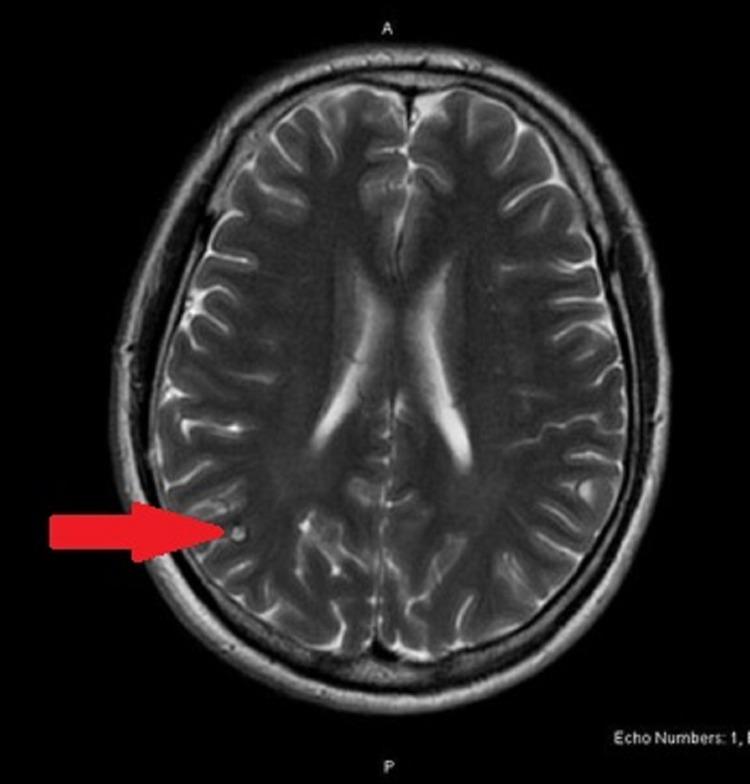

is a common cause of gastroenteritis and can also lead to serious complications such as dehydration, seizures, hemolytic uremic syndrome, and neurological complications. In this paper, we describe a case of a 39-year-old man who was admitted septic, with altered mental status and gastrointestinal symptoms. During the evaluation, he was found to have positive meningeal signs, non-anion gap metabolic acidosis, enteric panel positive for , positive IgG for , and pancolitis on computed tomography (CT) of the abdomen and pelvis. He was treated for infectious colitis and initially treated empirically for meningitis, but antibiotics were later discontinued due to rapid improvement of meningeal signs. To reduce the risk of disseminated infection, the patient was also treated for .

是肠胃炎的常见病因,还可导致严重并发症,如脱水、癫痫发作、溶血尿毒综合征和神经并发症。在本文中,我们描述了一例39岁男性患者,他因败血症入院,伴有精神状态改变和胃肠道症状。在评估过程中,发现他有脑膜刺激征阳性、非阴离子间隙代谢性酸中毒、肠道检查 呈阳性、 IgG呈阳性,腹部和骨盆计算机断层扫描(CT)显示全结肠炎。他接受了感染性结肠炎的治疗,最初经验性地接受了脑膜炎治疗,但由于脑膜刺激征迅速改善,后来停用了抗生素。为降低播散性感染的风险,患者还接受了 治疗。